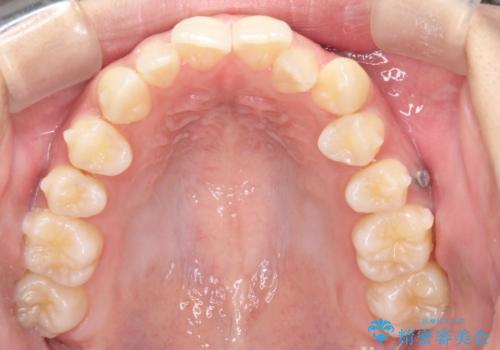

初診時の歯並びの状態としては、上下ともに全体に及ぶの中等度のがたつき(叢生)があり、全特に左上の前歯は1本だけ引っ込んでいる状態でした。

抜歯は行わず上顎の奥のスペースを利用して歯をスライドする方法の他に歯列弓の拡大やディスキング(歯と歯の間の隙間を作る処置)を行い叢生を改善しました。

歯の大きさの不揃いが原因の正中のズレは、ディスキング量を調整することで合わせています。